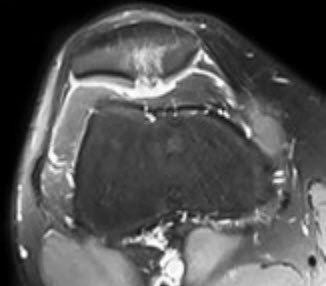

Ein 26-jähriger, sportlich aktiver Patient, der zuvor keine Kniebeschwerden hatte, erlitt bei einem Mountainbike-Sturz ein direktes Anpralltrauma des rechten Kniegelenks. Zunächst entwickelten sich eher leichte Beschwerden. Trotzdem war der Sportler in den Wochen nach dem Unfall in seiner sportlichen Aktivität und auch im Alltag aufgrund von Schmerzen und Schwellungszuständen am rechten Kniegelenk eingeschränkt. Da temporär durchgeführte physiotherapeutische Massnahmen keine Besserung der Symptomatik erbrachten, stellte sich der Patient bei seinem Hausarzt vor. Dieser liess folgerichtig eine Magnetresonanztomographie (MRI) des betroffenen Kniegelenks erstellen. Darin zeigte sich ein ausgedehnter Knorpelschaden im Bereich der Kniescheibenrückfläche (Abb. 1) bei ansonsten unauffälligem Binnenbefund des Kniegelenks.

Die Wassereinlagerung (Knochenmarködem) hinter dem Knorpelschaden weist auf einen frischen, unfallbedingten Knorpelschaden hin. Der Patient wurde an unsere Abteilung überwiesen. Sowohl klinische als auch bereits vorliegende radiologische (MRI) Untersuchungen wiesen in Zusammenschau der Anamnese auf den Knorpelschaden als Ursache der beschriebenen Symptome hin. Wir empfahlen einen operativen Eingriff zur Sanierung des Knorpelschadens.